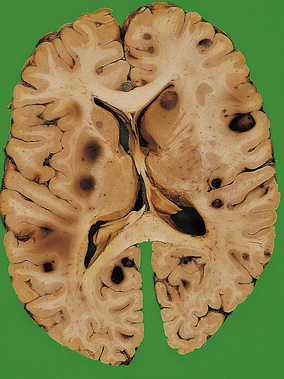

At a very early stage after cerebral infarction, no naked-eye abnormalities are apparent. However, 24 hours after infarction the affected tissue becomes softened and swollen, with a loss of definition between grey and white matter. There may be considerable oedema around the infarct, resulting in a local mass effect. Within 4 days, the infarcted tissue undergoes colliquative necrosis. Histology shows infiltration by macrophages, which are filled with the lipid products of myelin breakdown. Reactive astrocytes and proliferating capillaries are often present at the edge of the infarct. Eventually, all the dead tissue is phagocytosed to leave a fluid-filled cystic cavity with a gliotic wall (Fig. 26.10). Some infarcts are haemorrhagic, possibly due to reflow of blood through anastomotic channels. Anterograde degeneration of nerve fibres occurs distal to the site of infarction, for example in the ipsilateral cerebral peduncle in infarcts involving the internal capsule.

image

Fig. 26.10 Cerebral infarct: cystic change. In this old infarct in the territory of the right middle cerebral artery, the necrotic tissue has been phagocytosed to leave a cystic cavity lined by glial tissue.